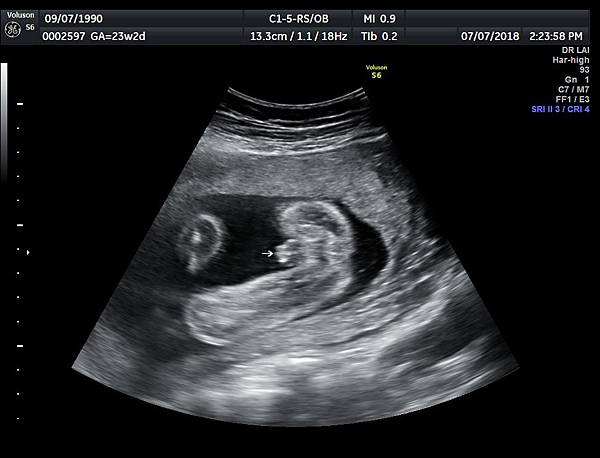

今天下午一位28歲第一胎的孕婦來診所做超音波檢查,之前他們一直認為懷的是女兒(檢查前資料顯示胎兒是女生);今天我的診斷胎兒是男生,但是懷疑有尿道下裂的問題(附圖 1~4),我的建議是抽羊水做染色體基因檢查,除了確定性別之外,也可以排除是否合併基因異常。

診斷尿道下裂常用的鬱金香sign(tulip sign)(附圖 10.11.),它的特徵就是龜頭陷入陰囊中間,胎兒如果是男生,一定要看到龜頭離開陰囊,這樣就沒有問題,每次遇到尿道下裂的個案時,我都會有一個感觸,男生如果能站著尿尿都要很感恩。